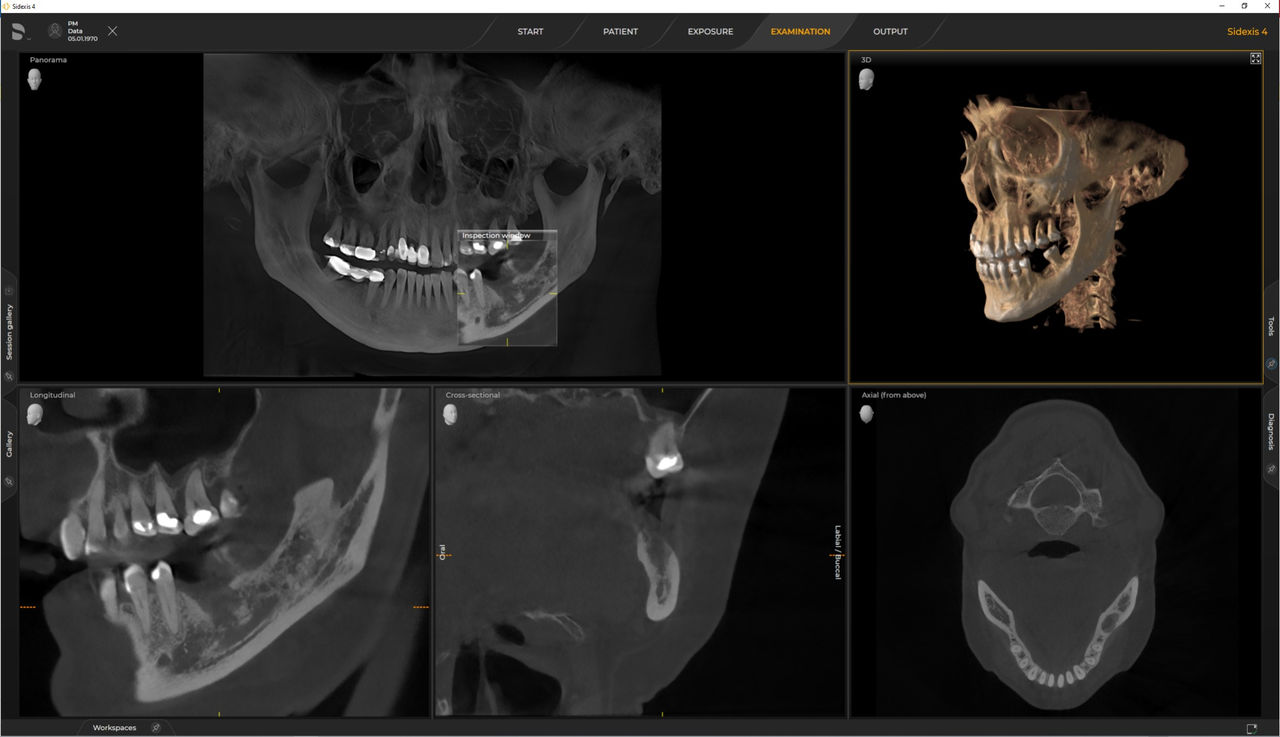

Das 2D-/3D-System mit großem Volumen und hoher Bildqualität für Praxen mit breitem Behandlungsspektrum. Gemeinsam mit Zahnärzten und Behandlern entwickelt, bietet Axeos von allen Dentsply Sirona Extraoral-Röntgengeräten das breiteste Behandlungsspektrum. Neben einer exzellenten Bildqualität und maßgeschneiderten 3D-Volumengrößen zeichnet sich das Röntgengerät durch einen hohen Patientenkomfort aus. Axeos bietet nicht nur Qualität bei Leistung und Komfort, sondern überzeugt auch durch sein preisgekröntes Design mit einem integrierten Aufbiss-Ordnungssystem und Ambient Light

Zahlreiche Volumengrößen sorgen für Flexibilität im Praxisalltag. Untersuchung eines bestimmten Bereichs oder Beurteilung der gesamten Bezahnung einschließlich der Kiefergelenke.

Mit dem Intelligent Low Dose-Modus erhalten Sie 3D-Bilder im Dosisbereich einer 2D-Röntgenaufnahme. Im HD-Modus werden während eines einzelnen Umlaufs bis zu 1.400 Einzelbilder aufgenommen und zu einem 3D-Volumen mit bis zu 80 μm zusammengeführt. Der Vorteil für Sie: rauschärmere Aufnahmen in hoher Auflösung.

Dentsply Sirona 3D-Röntgengeräte arbeiten exklusiv mit Sidexis 4 zusammen. Aber die Datenmigration von Sidexis XG zu Sidexis 4 ist sehr einfach. Wir empfehlen den Wechsel zu Sidexis 4, um die vollen Vorteile des digitalen Prozesses mit den neuesten Werkzeugen zu erleben.